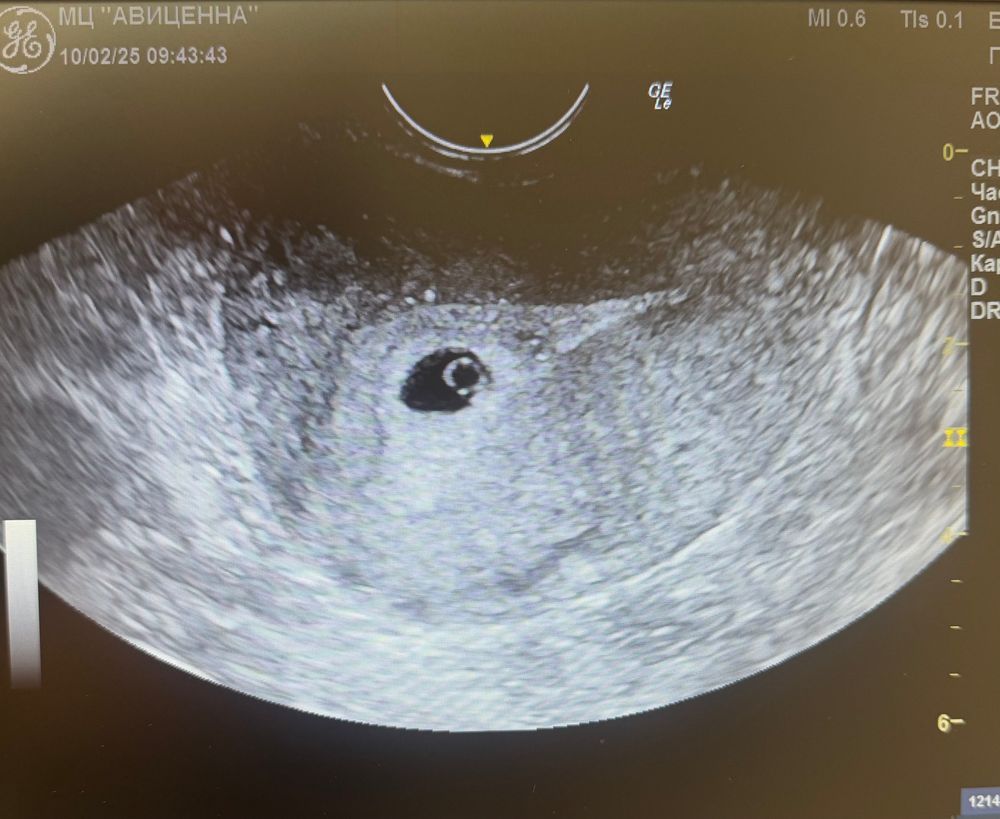

недели не эмбриона

4 5 недели не эмбриона 146 фото